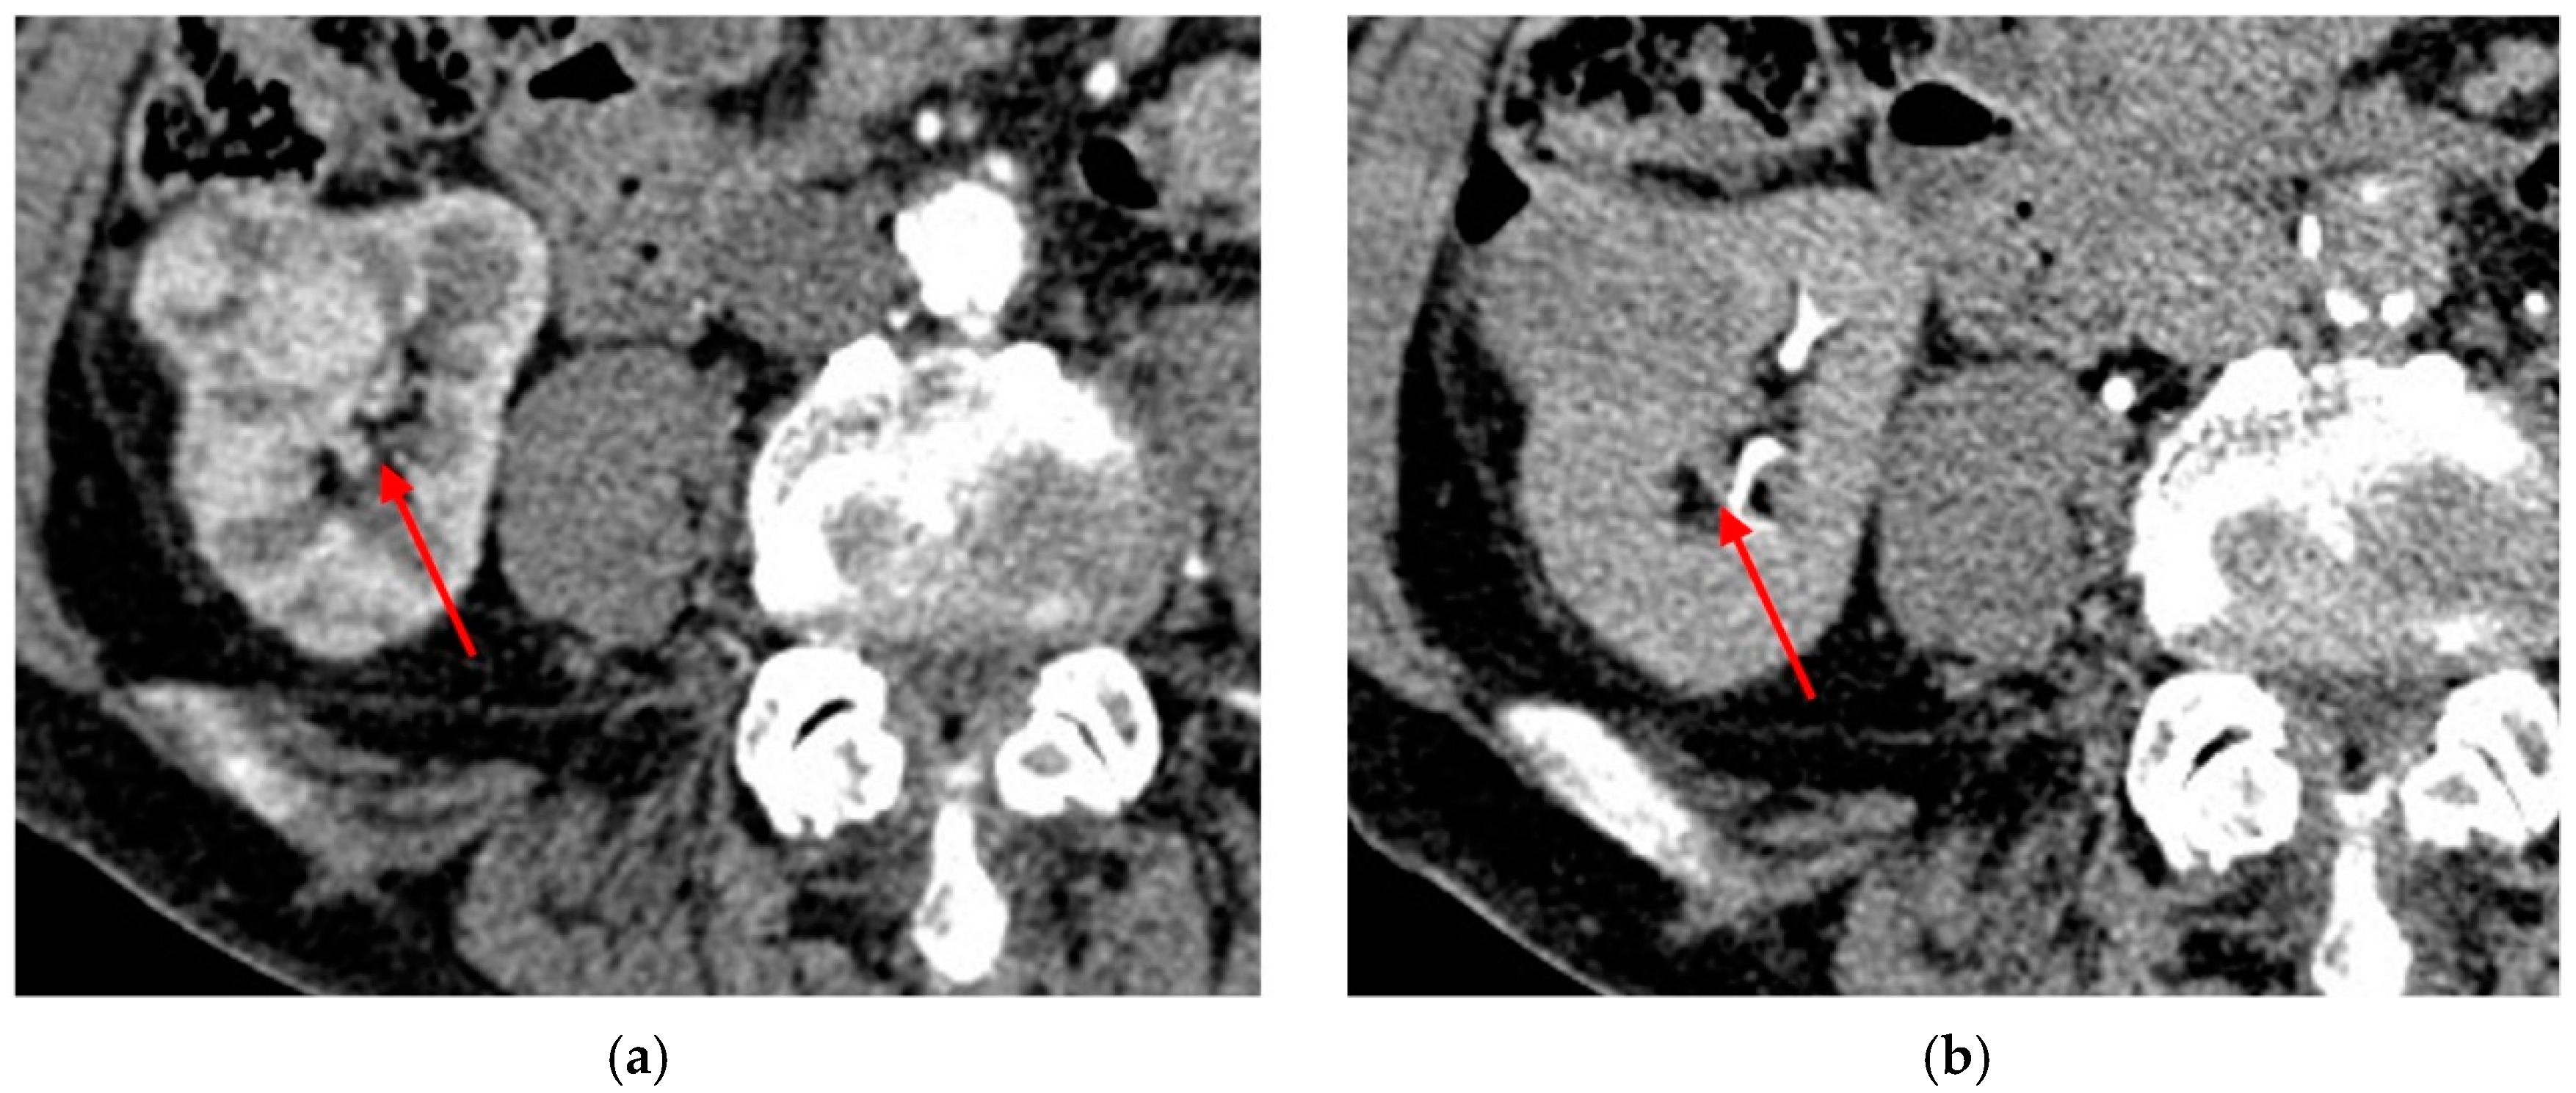

3.3. Chromophobe RCC